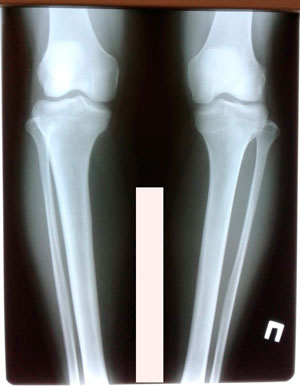

Исходник - 27 лет. Якутия.

Дата операции - 12.07.2019г.

Ротация справа.